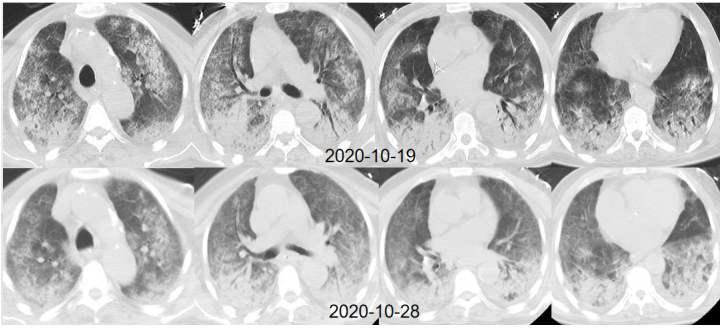

复查胸部CT可见病变较前进一步吸收(图9)

图片

图9 患者胸部CT改善情况